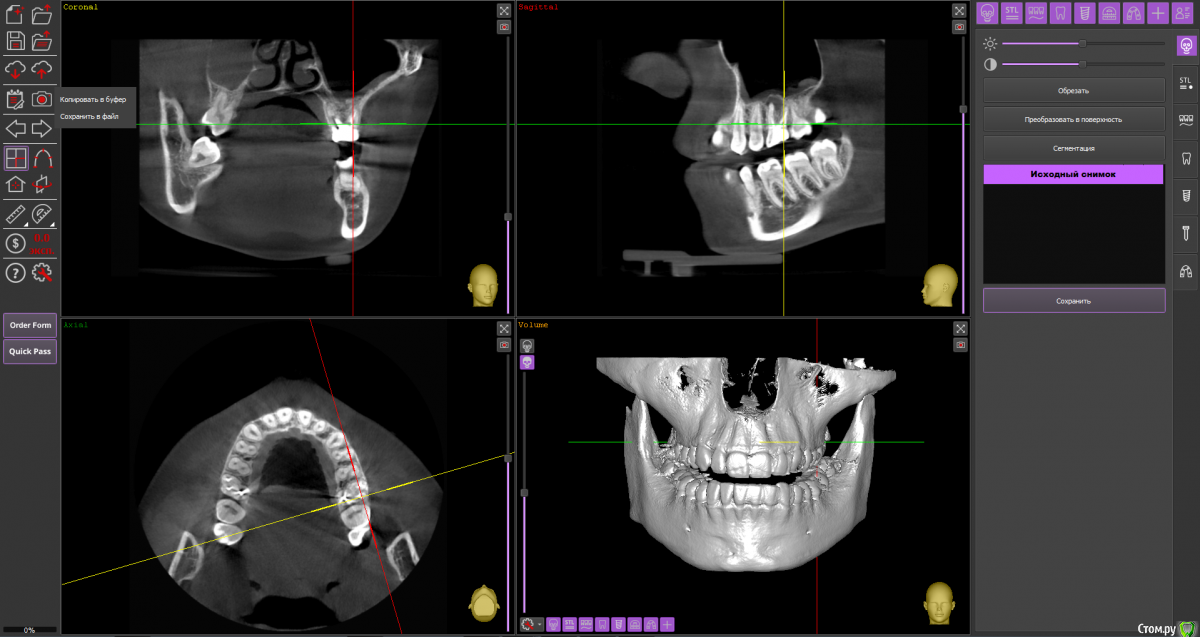

Ольга Вовк Опубликовано 10 февраля, 2021 Поделиться Опубликовано 10 февраля, 2021 Добрый день! Очень прошу помочь по таким вопросам:1. Верхняя шестерка справа - там киста перешедшая в гайморову пазуху (узнала это 4 месяца назад). Зуб ныл 2 года назад, тогда врач просто прописала Аугментин. Все прошло, но опять начал поднывать неделю назад (сейчас опять прошло). Была на консультации, сказали вырывать и прочищать пазуху нужно сейчас, и по приезду уже дальше разбираться. Как лучше быть, если я через неделю уезжаю на 4.5 месяца в страну, где никак не смогу продолжить лечение, а значит ставлю на паузу все на этот период.1. Удалить зуб сейчас, чтоб он зажил и через 4.5 месяца приехав сделать синус лифтинг и ставить имплант, или же ждать это время не удаляя зуб? 2. Не разрушится ли если сейчас не вырвать полностью костная ткань? 3. Можно ли не ставить имлпант, а сдвинуть 7 и 8 зуб к 5ому? Также вопрос по верхней шестерке слева - можно ли ее перелечить под микроскопом, или нужно делать резекцию? Разные врачи сделали разные выводы по нему Ссылка на архив файлов панорамного КТ - http://fayloobmennik.cloud/7414975 Спасибо вам, очень надеюсь на совет Ссылка на комментарий

wladdX Опубликовано 10 февраля, 2021 Поделиться Опубликовано 10 февраля, 2021 (изменено) Зуб 16, мне кажется, лучше удалить до отъезда. Насчёт ортодонтического перемещения 8-го и 7-го на место 6-го, необходимо с ортодонтом очно пообщаться, но на мой взгляд, хирургическое лечение будет более предсказуемым.Зуб 26 может оказаться непростым для эндодонтиста, но если доктор берётся и Вы ему доверяете, то начать стоит с повторного эндодонтического лечения с увеличением. Изменено 10 февраля, 2021 пользователем wladdX 2 Ссылка на комментарий

Ольга Вовк Опубликовано 10 февраля, 2021 Автор Поделиться Опубликовано 10 февраля, 2021 16_1.png 16_2.png 16_3.png 26_1.png 26_2.png 26_3.png 26_4.png Зуб 16, мне кажется, лучше удалить до отъезда. Насчёт ортодонтического перемещения 8-го и 7-го на место 6-го, необходимо с ортодонтом очно пообщаться, но на мой взгляд, хирургическое лечение будет более предсказуемым.Зуб 26 может оказаться непростым для эндодонтиста, но если доктор берётся и Вы ему доверяете, то начать стоит с повторного эндодонтического лечения с увеличением.Спасибо вам огромное! Я так понимаю, что если не удалить сейчас, то тогда к приезду (3 июля) уже совсем костной ткани не останется? Просто если сейчас удалить и будут осложнения, или соустье в гайморову, то я уеду и там не знаю что буду делать в такой ситуации(( Ссылка на комментарий

Irouil Опубликовано 11 февраля, 2021 Поделиться Опубликовано 11 февраля, 2021 останется? Просто если сейчас удалить и будут осложнения, или соустье в гайморову, то я уеду и там не знаю что буду делать в такой ситуации(( А если не удалить и у Вас случится гайморит - знаете? Я полностью согласен с wladdX, 1.6 удаляете срочно, с осложнениями после удаления вопросы решаете по факту их поступления, 2.6 перед отъездом тоже желательно просанировать. Ссылка на комментарий